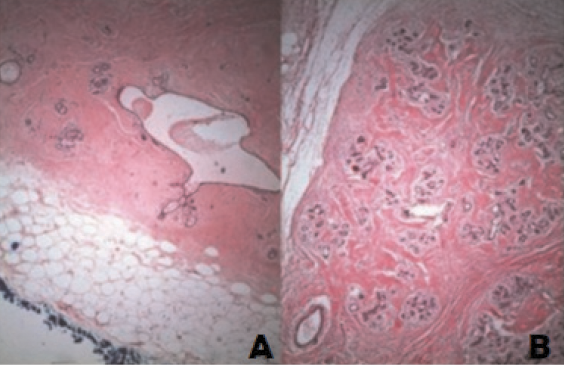

Microscopically, the lesion shows fibrotic stroma extending between individual breast lobules and adipose tissue in varying proportions with disorganized architecture (Figure 1). Adipose tissue is present in more than 90% of the lesions, and its volume generally accounts for 10–30% of the lesion volume [18]. The lesions may have variable amounts of smooth muscle, cartilage, or pseudoangiomatous stromal hyperplasia (PASH).

Figure 1 (A) and (B). Well-circumscribed mass with normal terminal ductal lobular unit, fat and hyalinized stroma, Haematoxylin Eosin (H&E), X 640. Image credits: Sevim Y, Kocaay AF, Eker T, Celasin H, Karabork A, Erden E, Genc V. Breast hamartoma: a clinicopathologic analysis of 27 cases and a literature review. Clinics (Sao Paulo) 2014; 69(8): 515–523. DOI: 10.6061/clinics/2014(08)03. Reused under the terms of the Creative Commons Attribution Non-Commercial License (http://creativecommons.org/licenses/by-nc/3.0/).